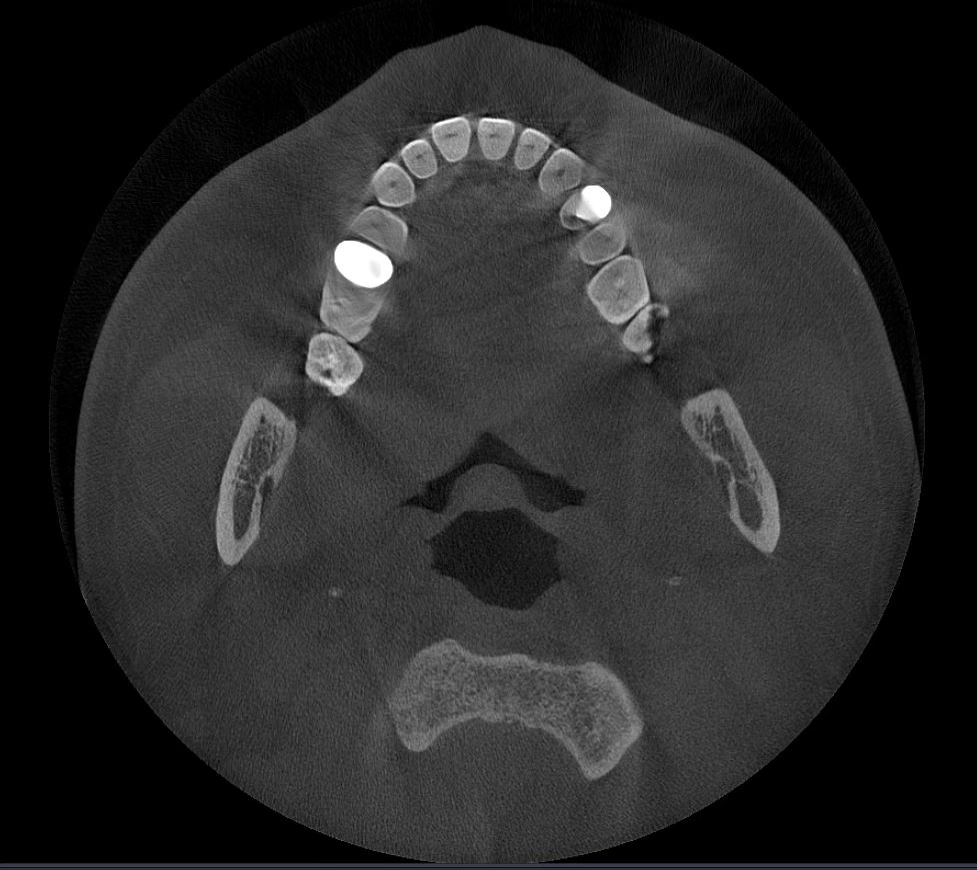

Los algoritmos matemáticos que reflejan las propiedades físicas y el avanzado motor de IA aprendido a partir de varios datos trabajan juntos para reducir el ruido y hacer que las estructuras dentales sean más claras.

Borra los artefactos metálicos y restaura con precisión las estructuras dentales, las coronas metálicas y los implantes basados en principios matemáticos.